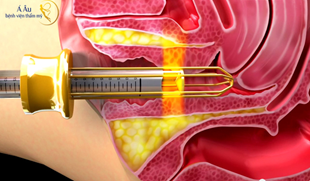

Ung thư cổ tử cung (CTC) là một trong những căn bệnh ung thư phổ biến ở Việt Nam,...

Danh sách các dịch vụ khám chữa bệnh như: khám sức khỏe phụ nữ tổng quát, tầm...